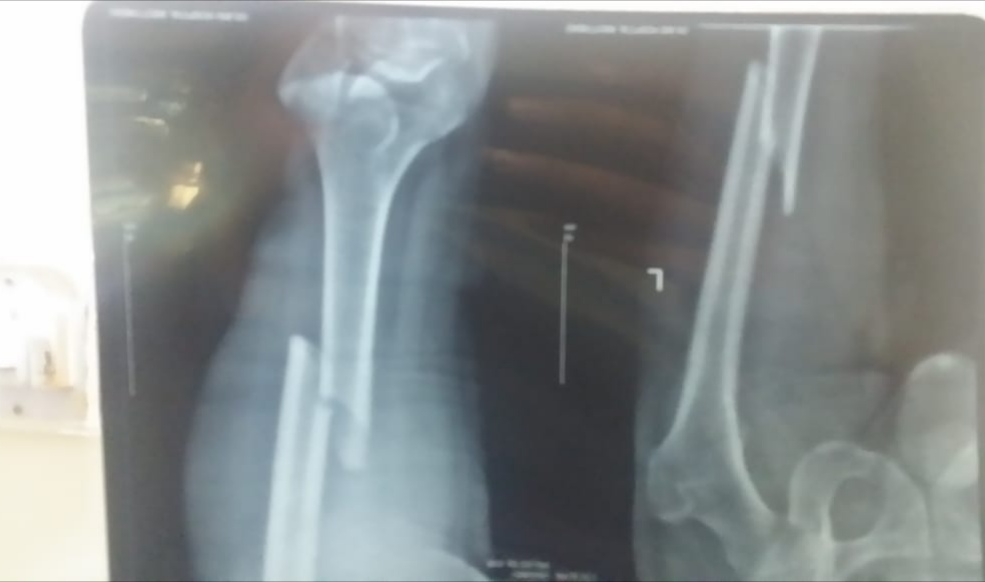

Please tag to an orthopedic surgeon.. My father age 60 had femur shaft fracture in Dec 2019 about 6 months ago where thigh bone has been broken in a angled line as shown in initial attached x ray. Dr. Implanted a rod with support in knee. In first 2 months he suffered from anxiety, but now he just feel uncomfortable in knee when he walk fastly or go up stairs. Now I attached today's x report could you please tell me the stage of healing process? Today one orthopedic surgeon advised that rod need to remove after couple of weeks because this rod is Biger than the usual used for these surgeries. But the surgeon who implanted gave us time period of one year to remove the rod. .should we go for rod removal? rod. I am attaching prescription and x ray in comments.

The nail is bending and the fracture line is visible,it is better to use cruthes while walking and wait for another six months

it's retrograde femur nailing. not a very poor procedure as it can damage knee articular cartilage. the nail is bent and as it seems there is shining callus which is going into consolidation. if weight bearing is painful then use a zimmer frame otherwise no issue. remove the nail after 1 year post op

This is retrograde nail and is done by opening up knee joint... So the distal part sometimes create problem with knee... Its realy to rem9ve the naip, so please avaoid stressea on stairs and squatting postures... Keep in touch with surgeon to get it removed early as the union is achieved fully